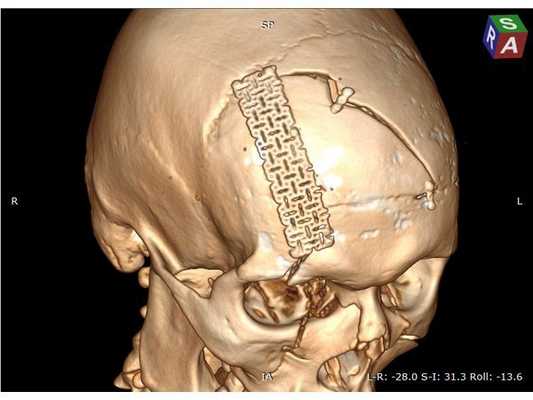

На контрольной КТ головного мозга в послеоперационном периоде видна положительная динамика: состояние после краниотомии, репозиции вдавленных фрагментов теменной кости, удаления субдуральной гематомы, регресса дислокации срединных структур стабильное.

Необходимо выполнить трепанацию черепа в лобной области; удалить, сопоставить и зафиксировать вдавленные костные фрагменты при помощи минипластин; удалить внутримозговую гематому; восстановить форму свода черепа с использованием металлической пластины. Ход операции: ⠀•⠀выполнен разрез мягких тканей в лобной области по Зуттеру, гемостаз моно- и биполярной коагуляцией по ходу скелетирования кости до уровня надбровных дуг, кожно-апоневротический лоскут откинут базально; ⠀•⠀открыт доступ к вдавленным костным фрагментам, в правой надглазничной области имеется повреждение костных фрагментов твёрдой мозговой оболочки и головного мозга, виден мозговой детрит (размозжённая мозговая ткань); ⠀•⠀с помощью краниотома костные фрагменты мобилизованы и удалены из раны, визуализировано повреждение твёрдой мозговой оболочки в области правой лобной доли; ⠀•⠀плотные сгустки крови и мозговой детрит аспирированы, отмыты физраствором и удалены, объём мозгового детрита — примерно 30 мл; ⠀•⠀произведён гемостаз с использованием биполярной электрокоагуляции, перекиси водорода и воска, твёрдая мозговая оболочка ушита и подшита по периметру костного дефекта нитью Викрил; ⠀•⠀самый крупный фрагмент кости уложен на место, костный дефект закрыт металлической пластиной; ⠀•⠀все костные фрагменты и сетчатая пластина фиксированы 10 винтами 1,5*5,0 мм и 2 минипластинами, операционная рана ушита послойно, кожа ушита непрерывным швом по Мультановскому, наложена асептическая повязка.